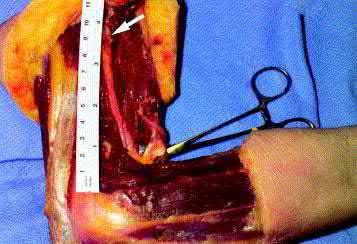

Figures A-C are the radiographs of a 26-year-old male who presents to the emergency department following a motocross accident. Two attempts at a closed reduction by the on-call orthopedic resident were unsuccessful. Figures D and E are the pre-operative axial CT-images that were obtained. The patient undergoes surgical fixation seen in Figure F. Limitations in post-operative dorsiflexion is likely influenced by which of the following?

This patient sustained a Bosworth fracture-dislocation and a posterolateral approach to the ankle is used to reduce the fibula back into the incisura and stabilize both the fibula and posterior malleolus. Loss of dorsiflexion is the most common arc of motion that is limited following this fracture pattern with posterior fixation.

The rare Bosworth fracture-dislocation is a posterior dislocation of the fibula which becomes entrapped behind the tibia. As demonstrated in this vignette, these injuries are extremely difficult to close reduce secondary to the ridge of the posterolateral distal tibia. The irreducible nature of this injury is a known risk factor for the development of compartment syndrome. The CT images further demonstrate fracture extension to the posteromedial rim (“posterior pilon variant”). In this situation, the only effective method to reduce the fracture is through an open posterolateral approach with the interval between the flexor hallucis longus and the peroneal tendons. This is the same approach that is utilized for fixation of the posterolateral fragment and fibula. Loss of dorsiflexion has been demonstrated following this fracture pattern with posterior fixation. The positioning of the plates in Figure F suggests the

utilization of a posterolateral approach.

Figures A-C: The initial radiographs reveal the posterior subluxation of the talus with associated posterior subluxation of the fibula without significant coronal plane deformity. This deformity should raise the suspicion of a Bosworth fracture-dislocation, especially if closed reduction is not successful. Figures D and E: Axial CT images demonstrating Bosworth fracture-dislocation of the fibula entrapped behind the tibia. Also, note the fracture extension to the posteromedial rim in this posterior pilon variant.

Figure F: Positioning of the plate suggests a posterolateral approach to address both the fibula and posterior malleolus fractures.